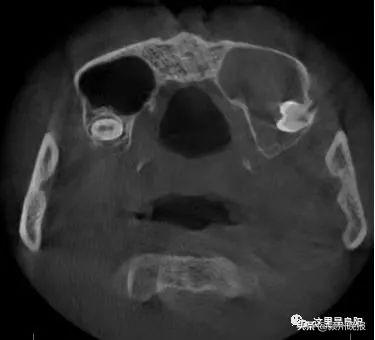

經(jīng)檢查

一顆智齒長(zhǎng)到了他的鼻子里

小劉的智齒位于竇腔底部

與鼻子上頜竇僅一膜之隔

而這層膜比蛋殼還要薄